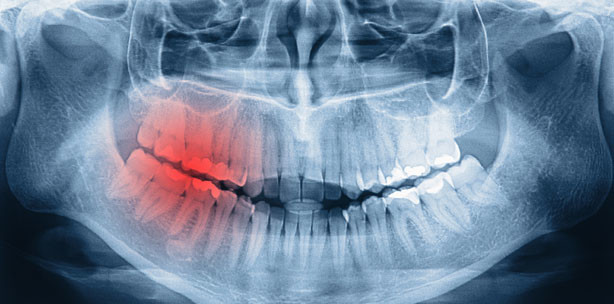

MKG-Chirurgie zwischen Implantologie und Tumorchirurgie

Foto: © Jessmine - Fotolia.com

Der 17. Kongress der Österreichischen Gesellschaft für MKG-Chirurgie verspricht mit dem Hauptthema „Die Mund-, Kiefer- und Gesichtschirurgie im Spannungsfeld zwischen Implantologie und Tumorchirurgie“ interessante Vorträge und Diskussionen.

Am Beispiel der Tumorchirurgie lässt es sich am Eindrucksvollsten aufzeigen zu welcher Spitzenmedizin Mund-, Kiefer- und GesichtschirurgInnen fähig sind. Durch Zusammenarbeit mit Nachbardisziplinen können die Resektionsgrenzen noch radikaler gesetzt werden. Multimodale Therapiekonzepte erfordern die Behandlung im hochspezialisierten Team.

Bei der Rekonstruktion erschaffen die Chirurgen zwar nicht aus einer Rippe eine Frau, aber mit trickreichen lokalen Lappentechniken und mikrochirurgischen Composite Lappen sind sie in der Lage zumindest große Gesichtsanteile dreidimensional anatomisch und funktionell zu rekonstruieren. Im Vergleich dazu könnte die Implantologie fast banal erscheinen. Wenn man jedoch die modernen Techniken des „backward planning“ mit Navigation oder Schablonenführung, minimalinvasive Augmentationstechniken (Schalungstechnik, hydraulische Sinuslifttechniken) und das ausgefeilte Weichgewebsmanagement betrachtet erkennt man, dass eine eigene Wissenschaft entstanden ist. Nur wer in der Lage ist auch dieses Feld auf höchstem Niveau abzudecken, wird hier weiter bestehen können.